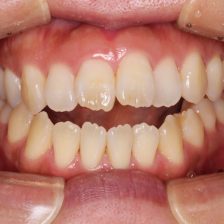

治療の前にはマイクロスコープや一眼レフカメラでお口の中を撮影して、現状をご確認いただきます。さらに患者さまのお悩みやご希望をしっかりうかがい、的確な治療法をご提案いたします。

むし歯治療

審美歯科

症例集